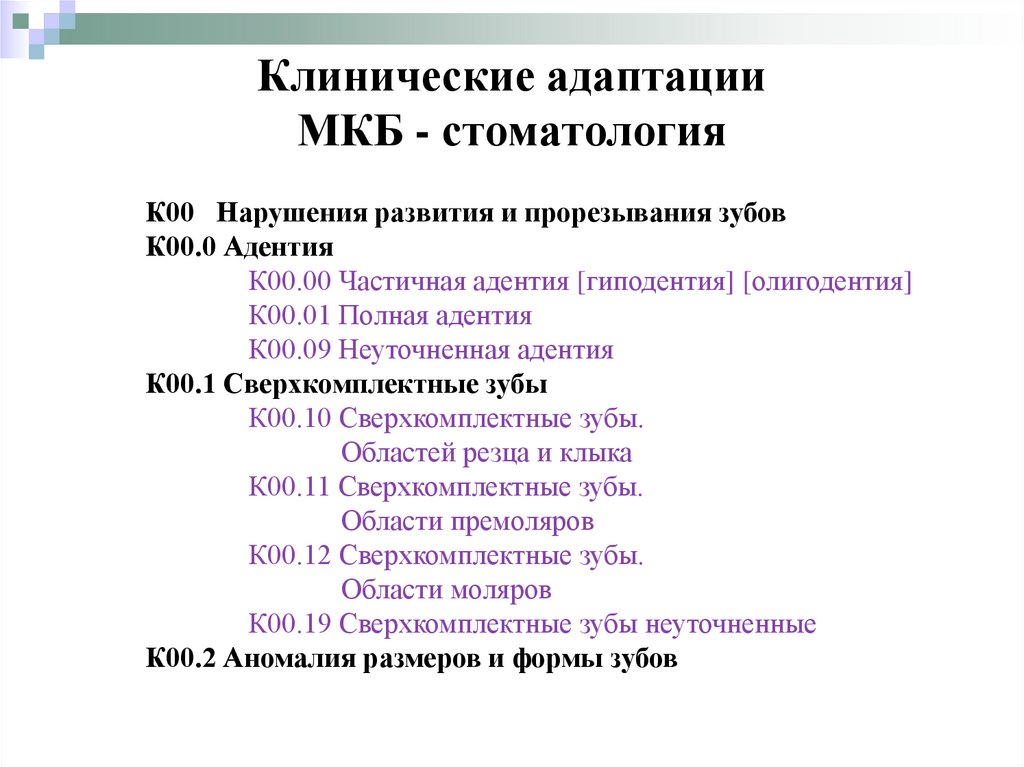

Код мкб 10 атерома головы

Код мкб 10 атерома головы 109 фото